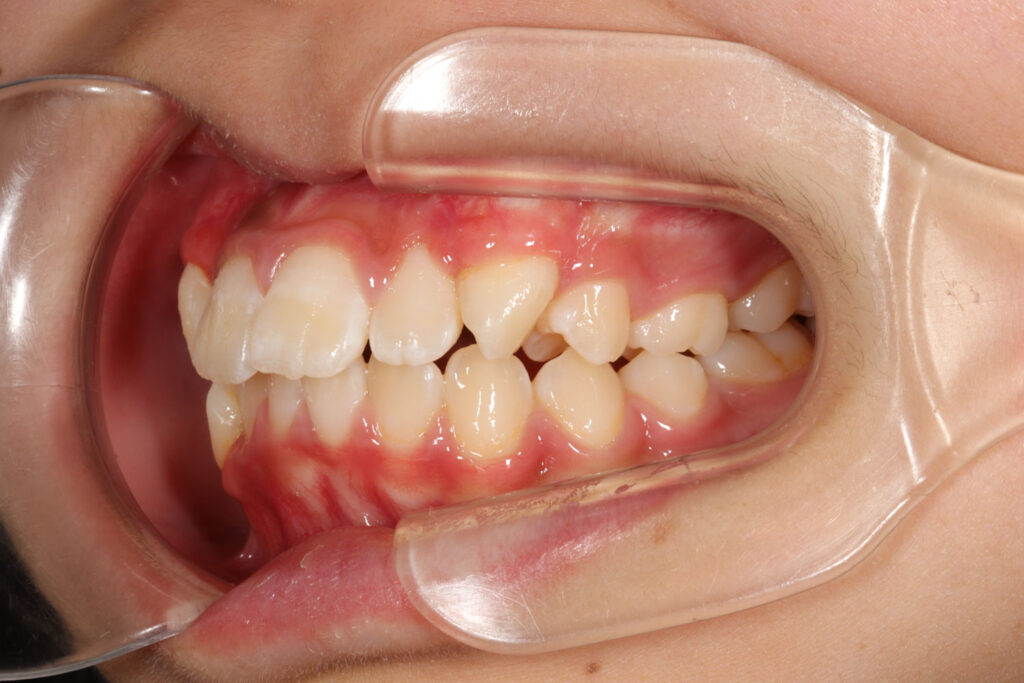

Before

年齢 10代

治療装置 上は裏側の矯正装置(ハーフリンガル)

治療内容 上下左右4本抜歯

治療期間 2年8か月

リスク 歯の移動に伴う痛み、歯肉退縮、歯根吸収、歯肉炎、虫歯

主訴 八重歯が気になる

症状 叢生(ガタガタ)

治療回数 33回程度

総額費用 125万円程度